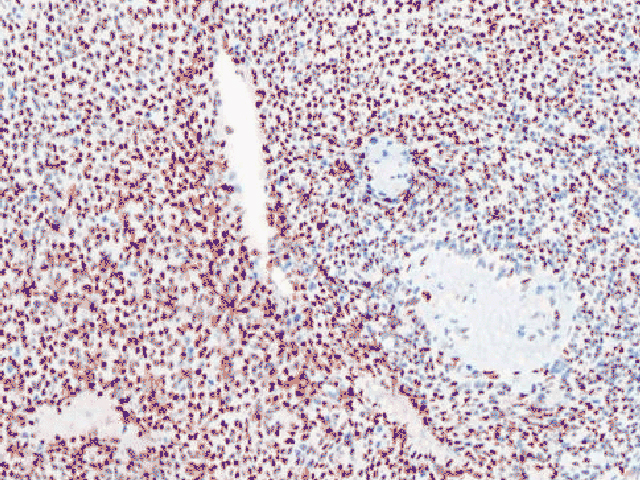

Transducin-like enhancer of split 1 (TLE1) is a member of the TLE family of transcriptional co-repressors that control the transcription of a wide range of genes and has been implicated in embryogenesis, hematopoiesis, and neuronal and terminal epithelial differentiation.15 TLE1 is involved in the Wnt/β-catenin signaling pathway, which is important in synovial sarcomas, and in the nuclear factor κB (NF-κB) pathway that regulates inflammation.15 TLE1 is an immunohistochemical marker for the diagnosis of synovial sarcoma and colon cancer.15 In addition, TLE1 overexpression has been observed in some cancers.15